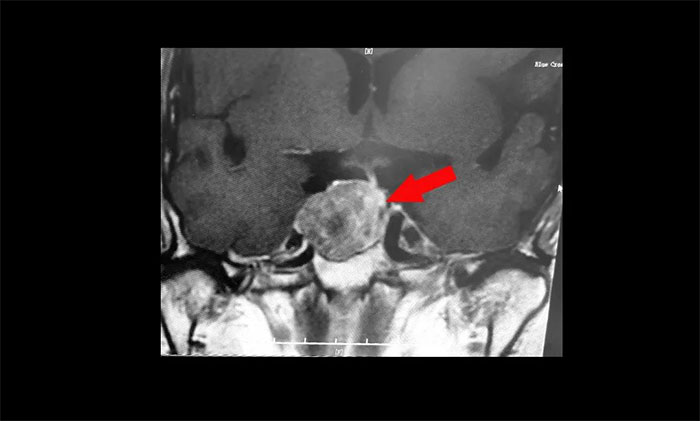

鞍區(qū)MRI平掃+增強(qiáng)顯示:蝶鞍顯著擴(kuò)大,鞍區(qū)見(jiàn)腫塊信號(hào),大小約29*19*24mm;垂體柄明顯縮短左偏;病變向鞍上生長(zhǎng),占據(jù)鞍上池,推移視交叉;向鞍旁生長(zhǎng),侵及右側(cè)海綿竇,右側(cè)海綿竇內(nèi)頸內(nèi)動(dòng)脈被推壓、包繞,右側(cè)頸內(nèi)動(dòng)脈海綿竇段較對(duì)側(cè)稍細(xì)。

▲ 腫瘤侵襲生長(zhǎng),包繞頸內(nèi)動(dòng)脈,knosp分級(jí)Ⅲ級(jí)

針對(duì)該患者,治療方式就是手術(shù)切除腫瘤,減除腫瘤壓迫。目前手術(shù)方式,主要有開(kāi)顱手術(shù)切除腫瘤和經(jīng)單鼻孔-蝶竇入路切除腫瘤。而該患者腫瘤如鴿子蛋大小,屬于垂體大腺瘤,并且侵襲生長(zhǎng),侵及右側(cè)海綿竇,右側(cè)海綿竇內(nèi)頸內(nèi)動(dòng)脈被推壓、包繞,knosp分級(jí)Ⅲ級(jí),向上已突破鞍隔壓迫視神經(jīng)、視交叉、下丘腦;向下侵蝕充滿蝶竇。